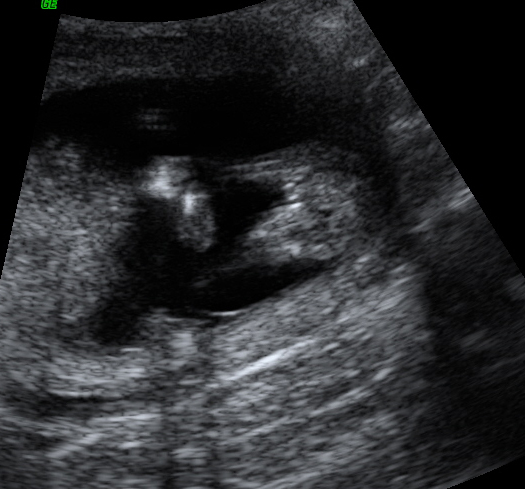

UPDATED --Just for fun, anyone want to take a guess